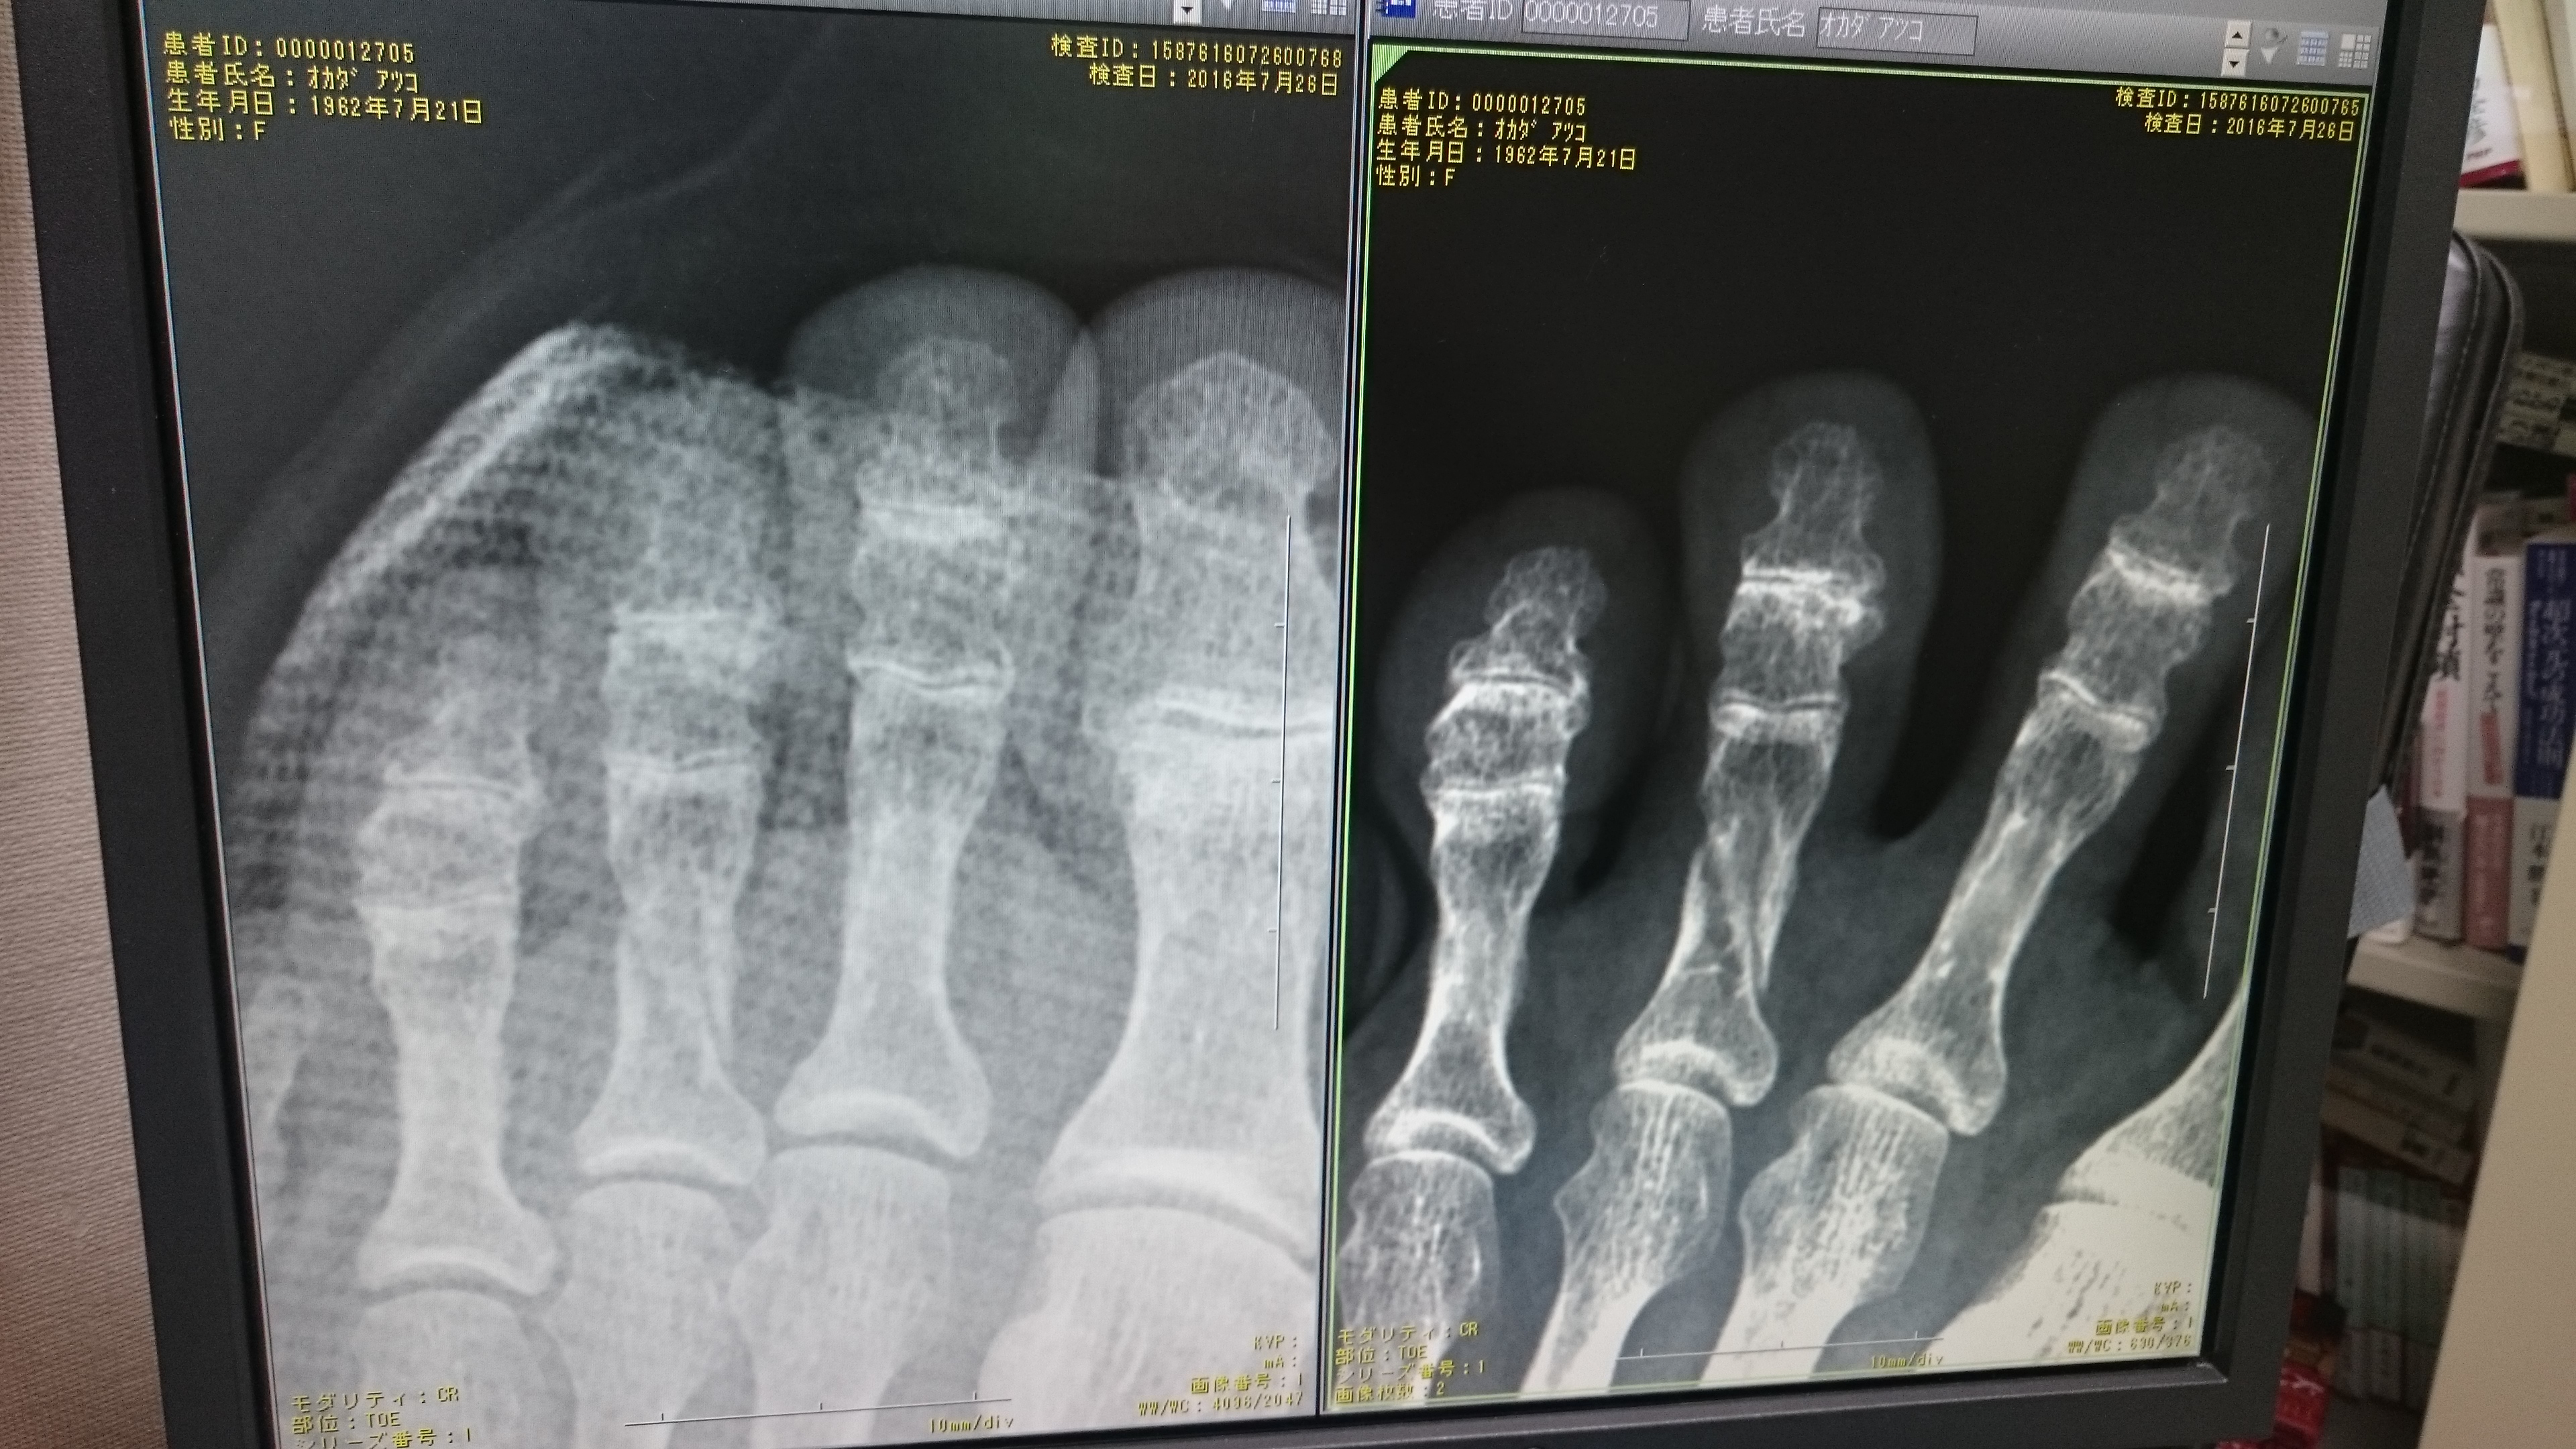

2016年7月26日 17:31 太陽クリニックブログ 足趾の打撲骨折 今日は足趾の打撲、骨折がやたら多かった。 骨折は無麻酔で(ごめんね)整復してシーネで固定した。 台所でとか、居間でとか、畳の部屋の段差でとか3人ほど同じ場所の怪我で来院した。 怪我には注意ですね。 コメントは受け付けていません。